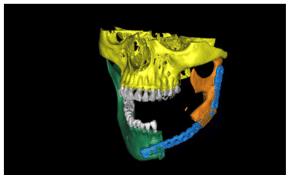

Due to the size of the lesion a mandibular titanium rod was placed to preserve the the lower portion of the mandible and part of the ascending ramus and condyle of the mandible (Figures 6,7,8) In the panoramic rx, the placement of the titanium rod can be seen to fix the ascending ramus with the condyle and the right side of the mandible with the resection to the level of the left lower canine (Figure 9).

Subsequently, a Walter Lorenz Titanium mesh (Figure 10,11) was used to contain the autologous bone that was obtained from the anterior iliac crest mixed with BMP2 morphogenetic protein (Cowell PLUS BMP), as well as Alogen bone mixed with growth factors and membranes with the Chuckron technique (Figure 12, 13,14)

The patient after surgery continued under observation and could not continue with her treatment due to the Covid epidemic, resuming the treatment on 03/02/2014 for the reassessment by CT the new bone formed in the area of surgery was observed by two programs Blues Sky Bio and Mimics of Materialise the values in Hounsfield units were determined in each of the CT slices at the sites planned for the placement of three implants, the values ranged from 209 U. Hounsfield to 1372 U. Hounsfield (Figs, 15,16,17,18).

In the CT scan, the bone regeneration of the morphogenetic protein BMP2 (Cowell PLUS BMP) and the growth factors with the Chucron technique were verified, managing to observe a good bone conformation, however, a bone formation was observed towards the upper part of the jaw that did not follow any anatomical pattern of the mandibular body and was attached to the mandibular body. (Figures 19,20, 21)